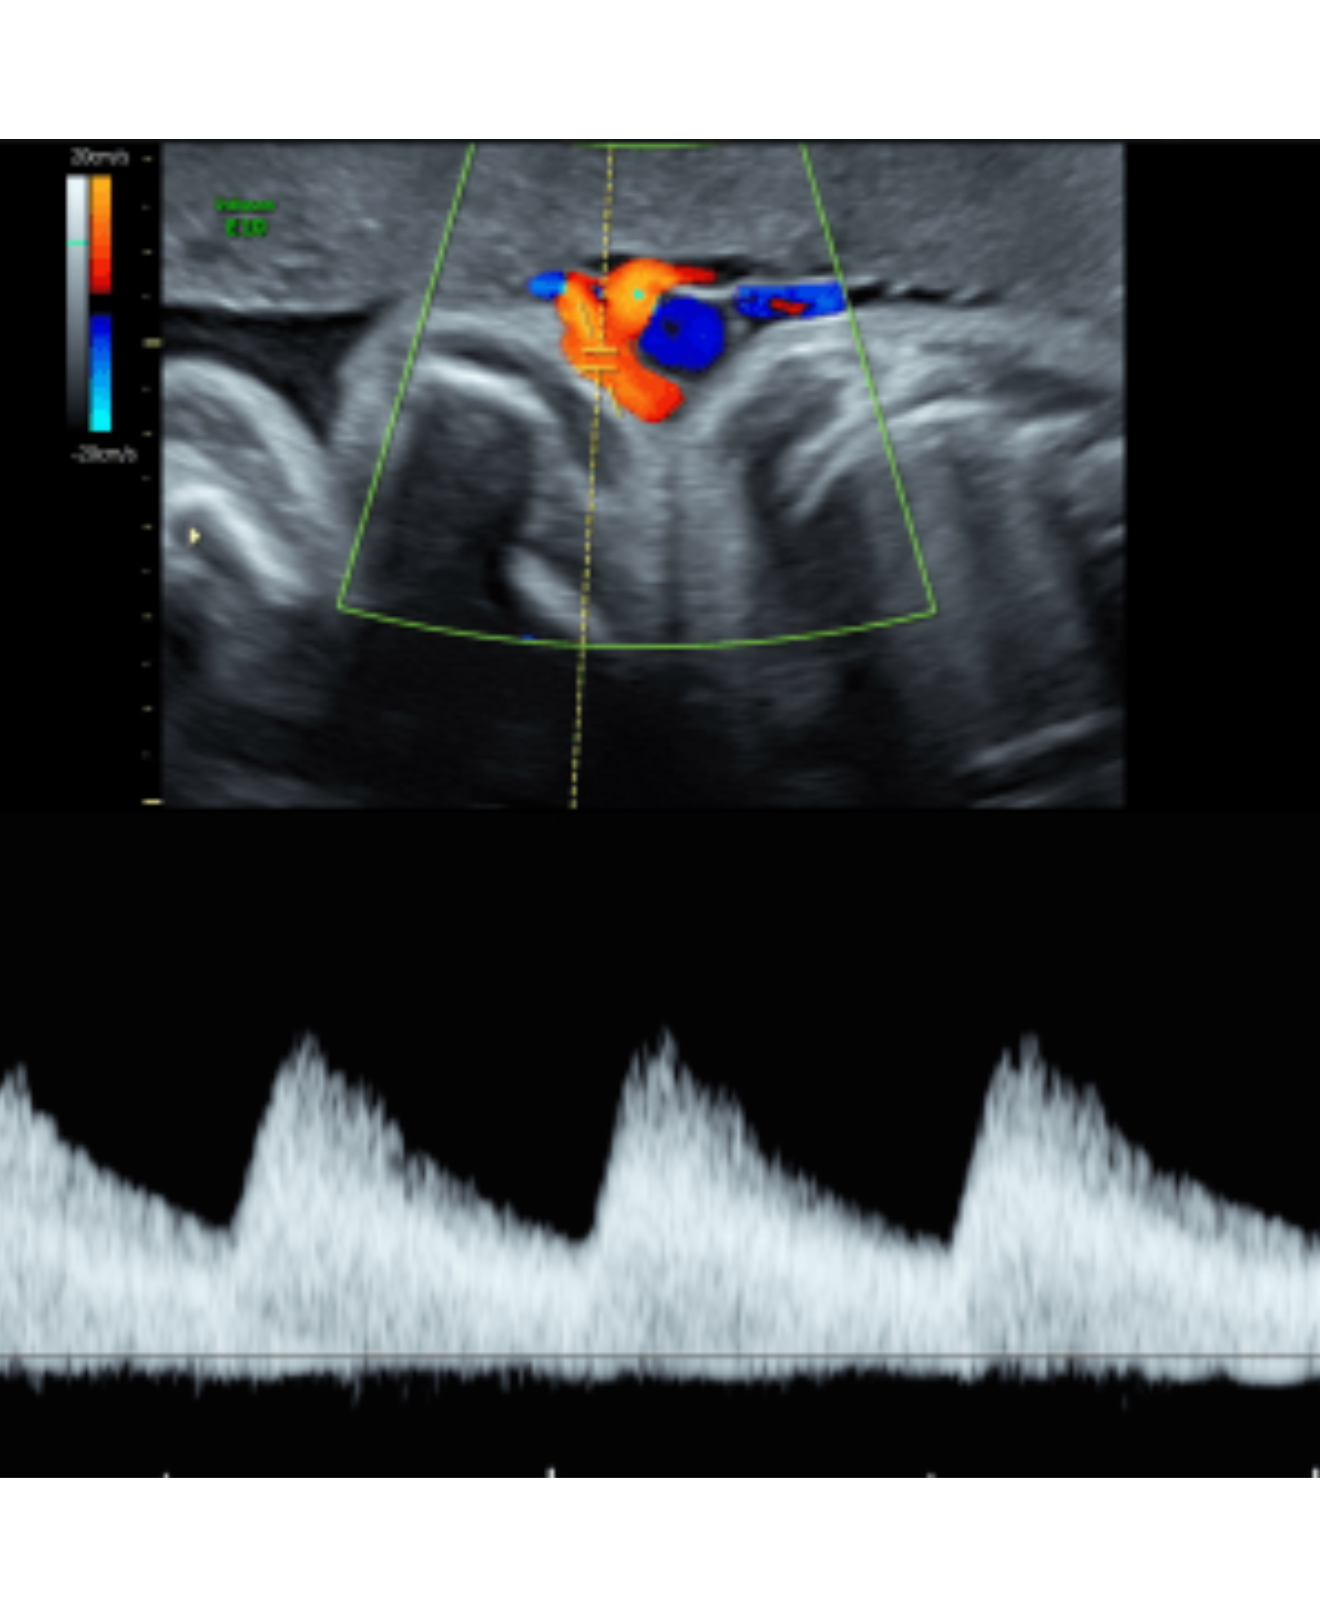

Doppler Fetal

Doppler de Arterias Uterinas

Doppler de Inserción Placentaria